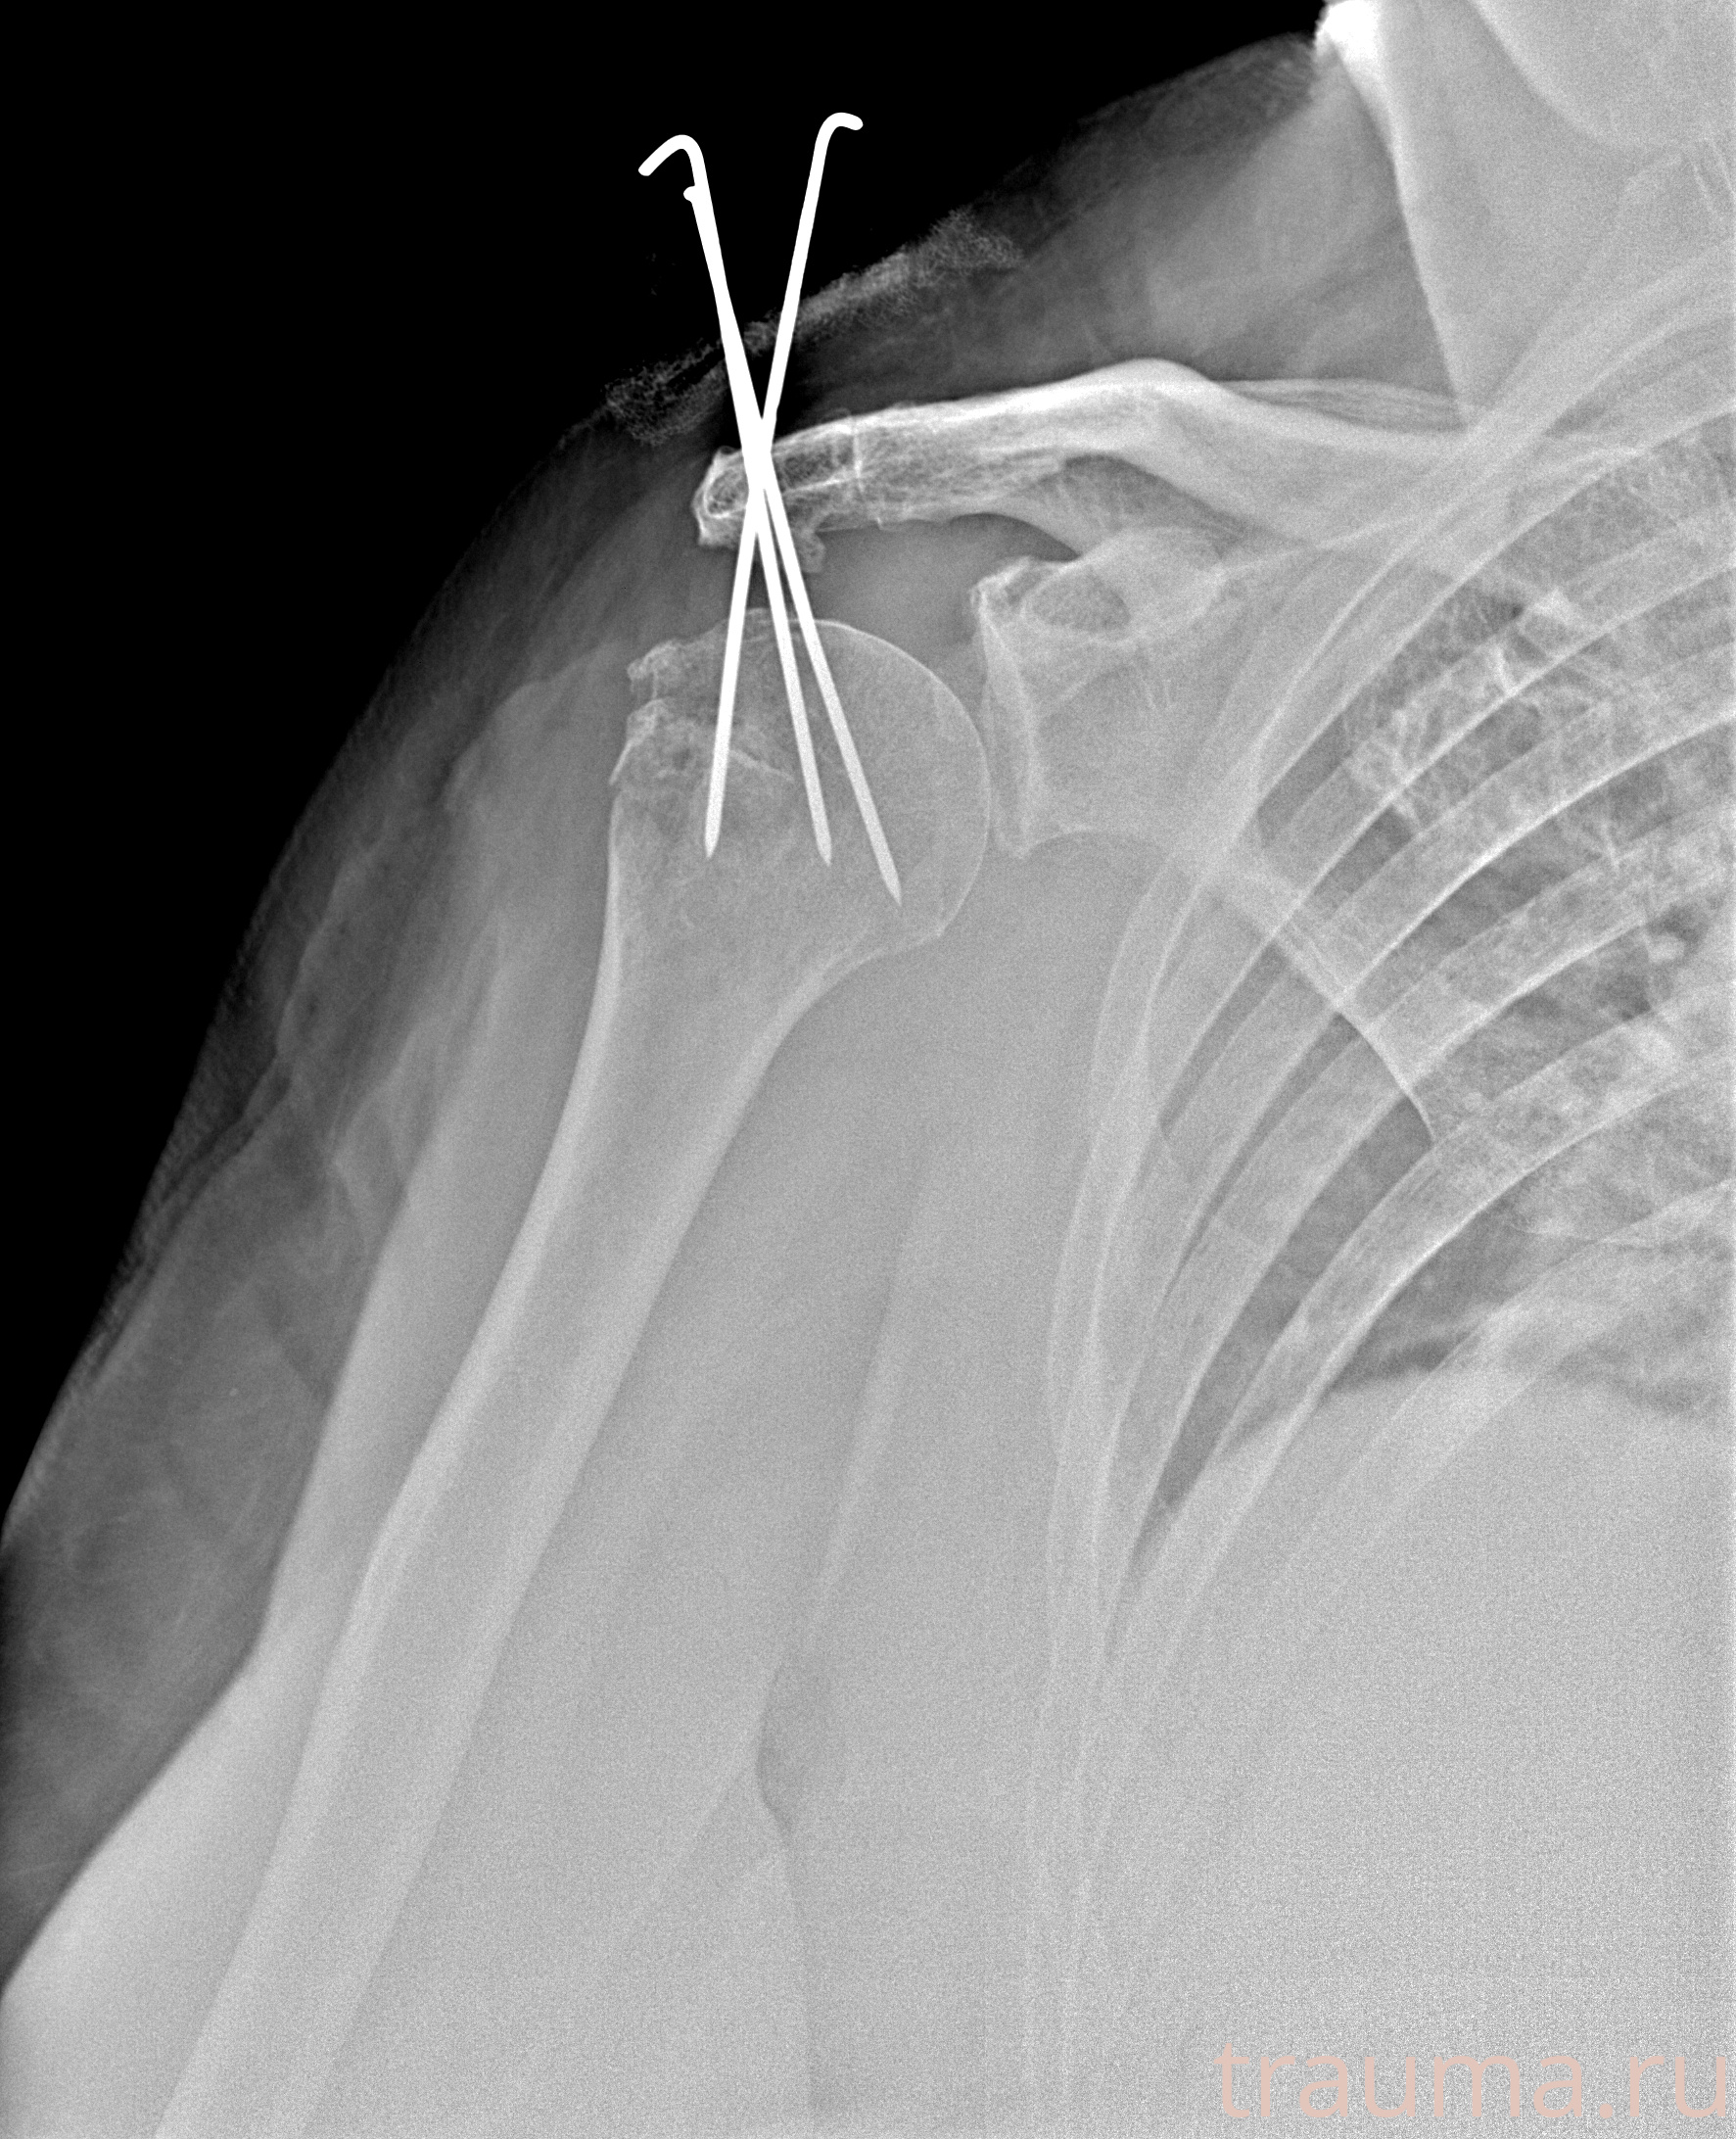

Рентгенограммы

Рентген на дому: по вашему адресу приезжает врач-рентгенолог, травматолог-ортопед с мобильным рентгеновским аппаратом, проводит диагностику травмы или заболевания, делает необходимые рентгенограммы, дает рекомендации по дальнейшему лечению. Получить качественные снимки в домашних условиях возможно благодаря уникальной методике, разработанной МосРентген Центром для института  Склифосовского